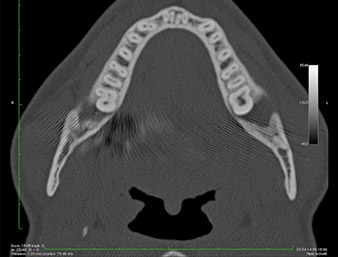

On voit sur l’image 3D (tomographie volumétrique numérique) que le reste radiculaire est en position disto-caudale au niveau de la transition de la partie horizontale vers la partie ascendante de la mandibule (Fig. 2).

Compte tenu de ses antécédents médicaux, notre patient (26 ans, non-fumeur) présentait de très bonnes chances

de réussite. L’OPG ayant révélé que le reste radiculaire était très proche du nerf alvéolaire inférieur, une tomographie volumétrique numérique a été effectuée en plus (6).